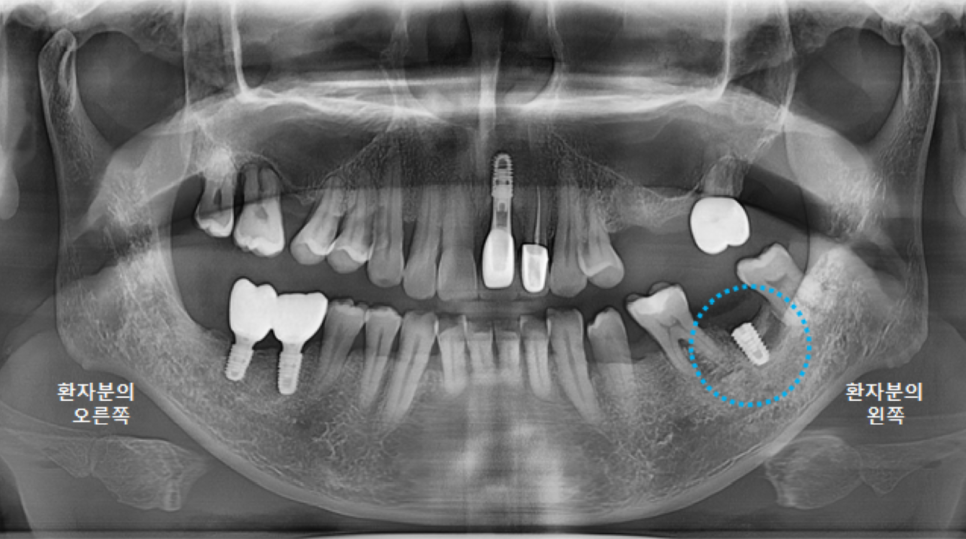

전체적인 구강 판단을 위해

파노라마 엑스레이 사진을 찍었습니다.

왼쪽 큰앞니도 빠져있지만,

오른쪽위 큰어금니, 오른쪽 아래 큰어금니도 발치된 상태였고,

왼쪽 위 브릿지 상태도 좋지는 않았습니다.

왼쪽 아래 큰어금니 하나는 뿌리만 남은 상태였어요.